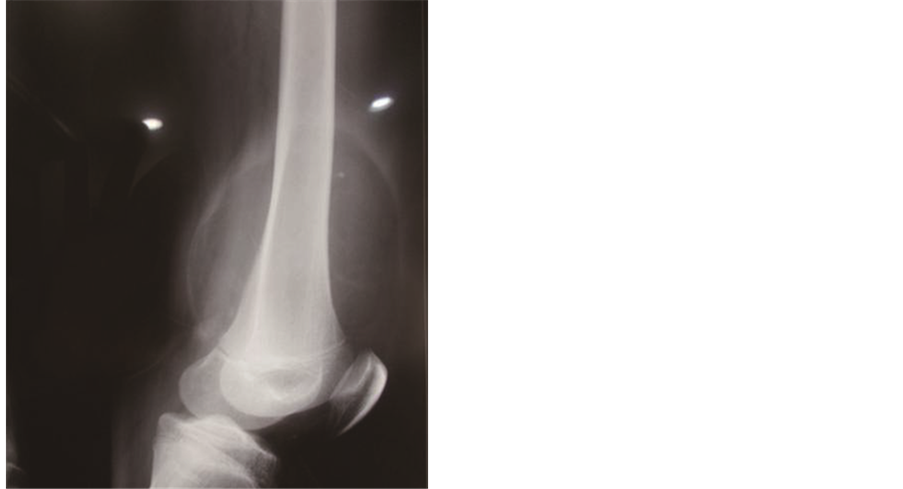

Conventional radiographs of the left thigh showed the presence of a spiculated periosteal bone formation in the antero medial face of the distal region of the femur and an increase in the amount of soft tissue with a radio density characteristic of fatty tissue (radiolucent image) (Figure 1) [4] -[6] .

Figure 1. (a) and (b) showing increased perisoteal reaction associated with an increase of adjacent radioluscent soft parts.